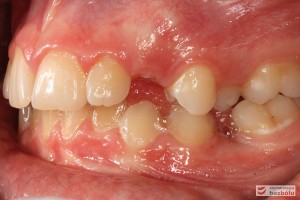

Rodzice zgłosili się z pacjentem celem rutynowej kontroli ortodontycznej. Wykonano OPG i po analizie modeli diagnostycznych stwierdzono brak miejsca dla wyrzynania dolnej prawej piątki stałej oraz zwężenie szczęki wraz z rotacją górnych zębów szóstych. W łuku górnym w pierwszym etapie leczenia zastosowano Rotator, celem odrotowania 6-tek stałych oraz ekspansji łuku w wymiarze poprzecznym. Następnie zamontowano aparat stały metalowy do uszeregowania zębów w łuku. W łuku dolnym miejsce odtwarzano stosując aparat stały i odpowiednią mechanikę leczenia. Leczenie aktywne trwało 3,5 roku, po czym zastosowano terapię retencyjną (retainer stały w żuchwie oraz Płytkę Hawley’a w szczęce).